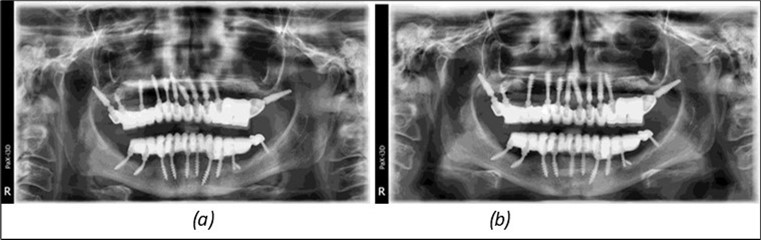

Figure 14.Rx panoramic final situation control: (a) Panoramic X-ray with the addition of a distal BCS implant in quadrant 3 at 11.2022; (b) Control X-ray, 10.2023.

Figure 15.Follow-up panoramic X-ray 09.2025

Results

The results of rehabilitation treatment with corticobasal and compressive implants with a polished surface after the failure of two stage implants were highlighted over a period of 3 years and 3 months as being very good (Figure 14, Figure 15), with the patient completing a satisfaction survey in this regard. Certainly, it is necessary to continuemonitoring these results in the long term.